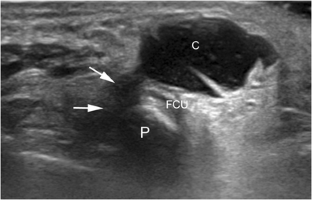

Fig. 1